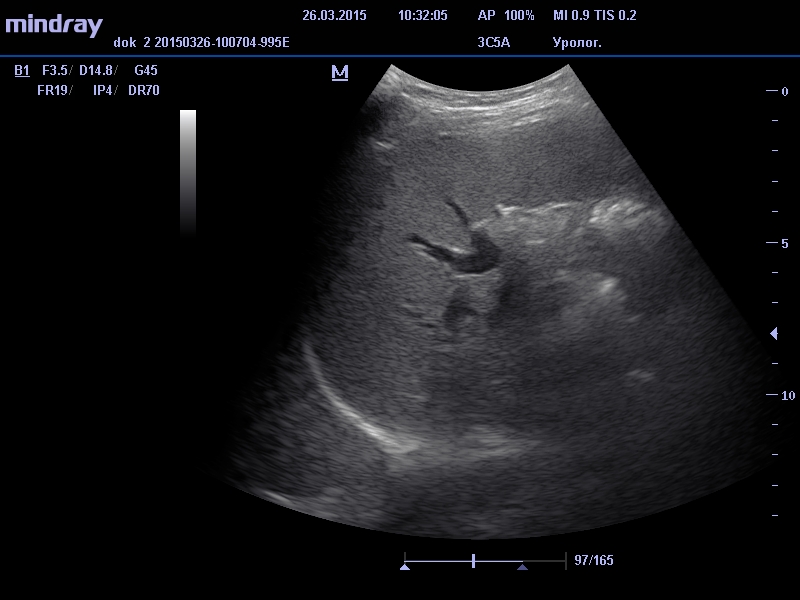

Процедура проводится в положении пациента на правом боку на высоте вдоха (т.е. необходимо задержать дыхание на вдохе), иногда врач может попросить изменить положение или подняться в полный рост для улучшения визуализации.

Нормальные показатели при УЗИ селезенки – форма чаще серповидная, ровные и четкие контуры, средняя эхогенность (равна или чуть ниже эхогенности не измененной печени), мелкозернистой однородной структуры. Размеры нормальной селезенки подвержены колебаниям, при этом максимальные : длина до 11 см, передне-задний размер до 4,5-5 см, селезеночный индекс от 15 до 23 см кв. Диаметр селезеночной вены в области ворот селезенки до 8 мм, диаметр селезеночной артерии до 2 мм.